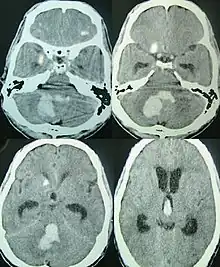

CT scan of a spontaneous intracerebral bleed, leaking into the lateral ventricles

Spontaneous ICH with hydrocephalus on CT scan[22]